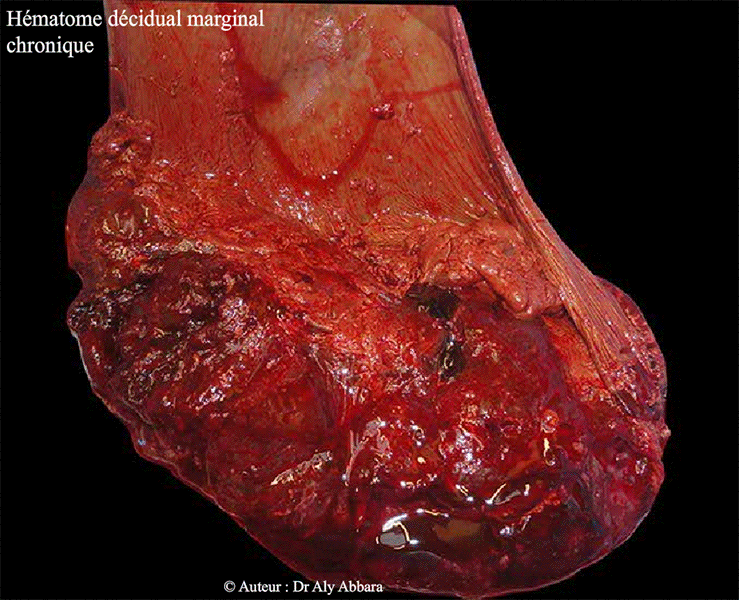

| Placenta : hématome marginal décidual chronique (hématome latéro-placentaire) Accouchement par voie naturelle après une mise en travail spontané à 39 semaines d'aménorrhée. |

| L'évolution de la grossesse fut marquée, dès le début du deuxième trimestre, par des métrorragies répétitives avec la mise en évidence, par échographie, de la formation d'un hématome marginal décidual (habituellement par rupture d'une veine utéro-placentaire) au niveau du pourtour du pôle inférieur du placenta (à insertion postérieure, non prævia). L'examen macroscopique du placenta, montre la présence d'un ancien hématome marginal, au niveau de son pourtour ; il est formé de caillots organisés (infiltré par des dépôts de fibrine), avec l'imprégnation des membranes amniotiques par l'hème oxydé, donnant à ces membranes une coloration ferreuse. |